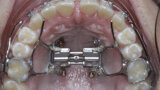

New Age orthodontics and orthopaedics with temporary anchorage devices